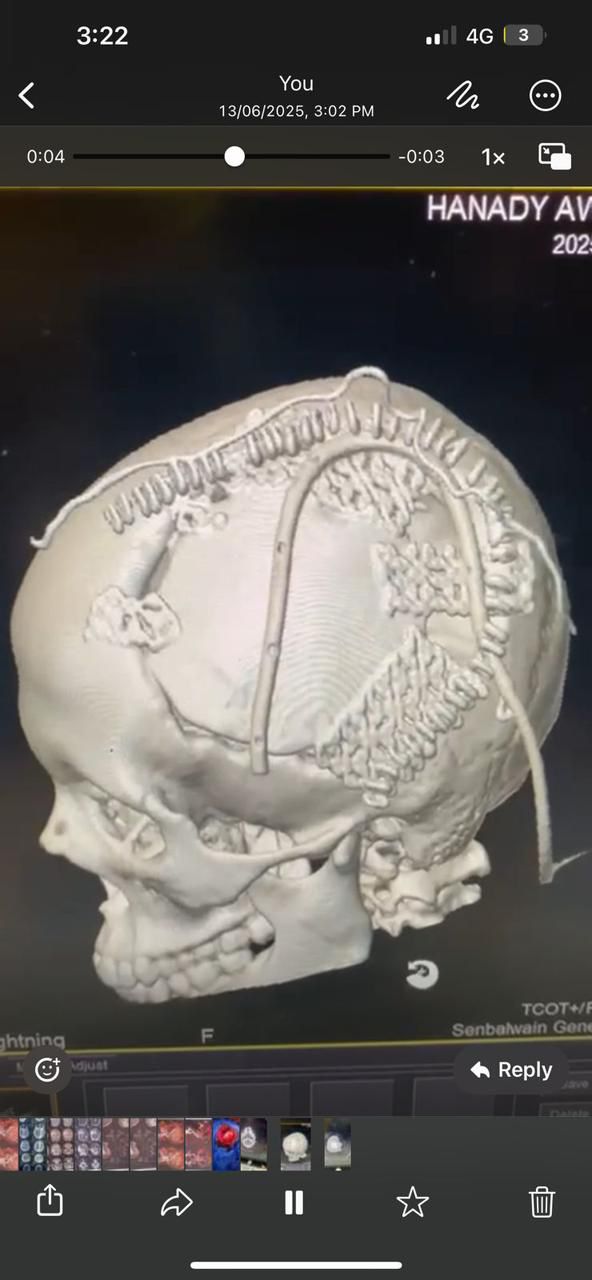

وقد أجريت للمريضة الفحوصات الطبية اللازمة، شملت: أشعة مقطعية على المخ ورنين مغناطيسي على شرايين وأوردة الدماغ وتكوين ثلاثي الأبعاد لشبكة الشرايين الدماغية.

وبعد استقرار الحالة، تقرر إعادة زرع عظام الجمجمة من التجويف البطني إلى موضعها الأصلي، لكن نتيجة لاحتمالية حدوث ضمور بالعظام المزروعة، تم تجهيز شبكة من التيتانيوم ثلاثية الأبعاد لترقيع الجمجمة بالشكل المناسب.

وتمت العملية بنجاح، عبر فتح الجمجمة بطريقة تجميلية تراعي الحفاظ على نمو الشعر، مع تثبيت شبكة التيتانيوم لإعادة الشكل الطبيعي للرأس.